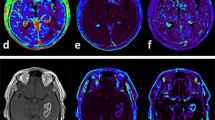

This study was approved by the institutional review board (IRB), which waived informed consent. A total of seventy-three AA patients who had undergone preoperative DCE and DSC MRI and received standard treatment, including partial resection or biopsy followed by radiation therapy, were included in this retrospective study. Based on Response Assessment in Neuro-Oncology (RANO), patients were sorted into progression (n = 21) and non-progression (n = 52) groups. Tumor boundaries were defined as high-signal intensity (SI) lesions on fluid-attenuated inversion recovery (FLAIR) imaging, where we analyzed mean pharmacokinetic parameters (Ktrans, Vp, and Ve) from DCE MRI and contrast leakage information (mean extraction fraction (EF)) from DSC MRI.